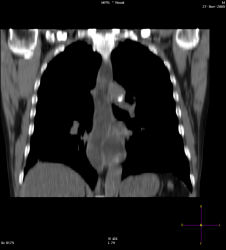

Добрый вечер, Валентин Львович. Я тут тоже немного оклемался от ОРВИ, появились силы выстовить случай. Данная демонстрация немного с подвохом, проанализируйте ещё раз рентгенограммы, более внимательно.

Видна полость напоминающая "абсцесс" справа, но это стандарта исследования не меняет.

Загадка кроется в средостении, а именно в заднем отделе средостения.

Мой коллега после МСКТ-ОГП, решил почему то о наличии фиксированнай грыжи диафрагмы, пациент попал ко мне на R-скопию пищевода и желудка:

Результат МСКТ:

Пациент поступил в стационар(отеделение терапии) с Ds: Внегоспитальной правосторонней пневмонией. После того как мой коллега описал при поступлении цифровые R-граммы ОГП, отметив о наличие фиксированной грыжи пищеводного отверстия дифарагмы(под вопросом), клиницисты сразу направили пациента на КТ с предворительным обоснованием: пневмония, абсцесс, ГПОД? И только спустя через 3-4 дня после МСКТ, как только пациент был прокунсультирован хирургом, его направили ко мне на R-скопическое исследование. МСКТ-делалось только один раз.